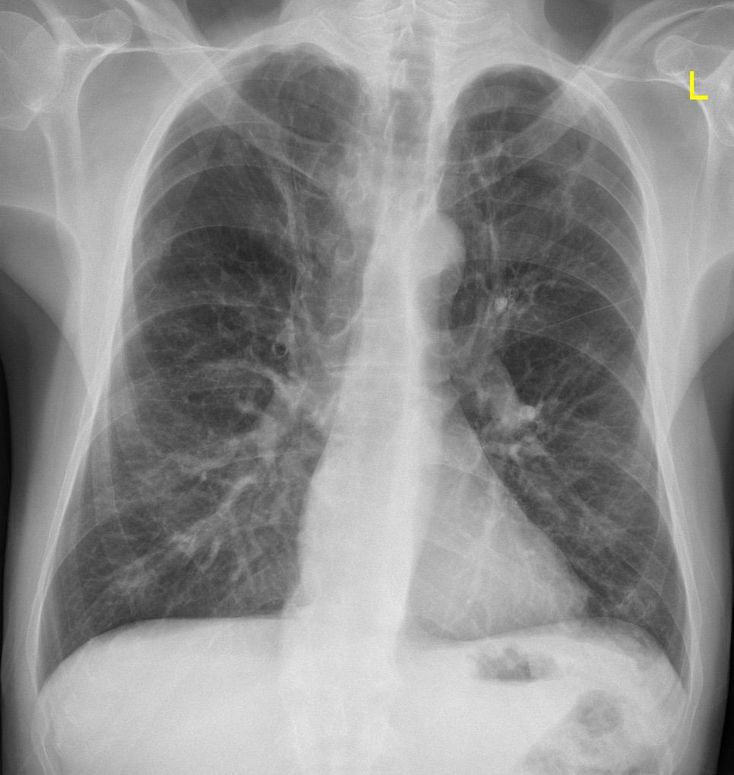

Emphysema

Lung

Chestxray

Diffuse in right upper lobe